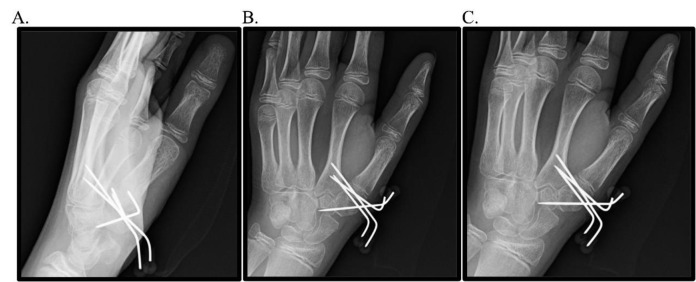

小儿班尼特等效型骨折是一种罕见但又重要的发病率和诊断复杂性的来源。尽管儿科患者具有显著的重塑潜力和弹性,但如果处理不当,这些损伤会带来多种后遗症,如残余畸形、疼痛、功能限制和前瞻性加速关节病。鉴于文献的缺乏和前瞻性、严格的试验的缺乏,这些损伤的最佳管理仍然存在争议。本研究展示了作者对两例儿童班尼特等效骨折的经验,一例保守治疗,一例手术治疗,强调了提供者在识别和治疗这些损伤时保持警惕和注意力的必要性。

Pediatric Bennett-equivalent type fractures represent an uncommon yet consequential source of morbidity and diagnostic complexity. Despite the remarkable remodeling potential and resiliency of the pediatric patient population, if managed inappropriately, these injuries are associated with multiple sequelae such as residual deformity, pain, functional limitations, and prospective accelerated arthrosis. Given the paucity of literature and absence of prospective, rigorous trials, the optimal management of these injuries remains contentious. The present study exhibits the authors' experience with two pediatric Bennett-equivalent fractures, one managed conservatively and one operatively, highlighting the necessity for provider vigilance and attentiveness in recognizing and treating these injuries.